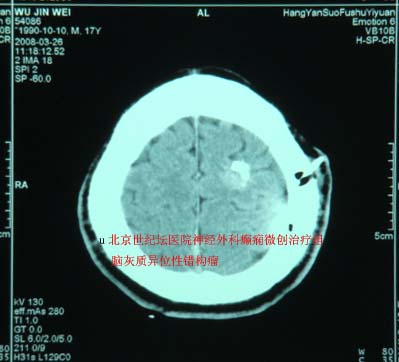

典型病例-脑灰质异位症

脑灰质异位症1例

脑灰质异位